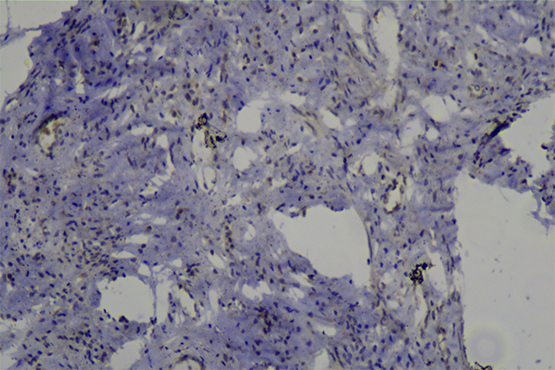

显微镜下的病理世界——肾脏切片

常用的病理诊断方法为有——组织学检查,病变组织制成厚约数微米的切片,通常用苏木精·伊红染色(HE染色),或其他方法染色后,用光学显微镜观察其微细病变。

这次,老师使用的仪器为明美生物显微镜ML31, 采用无限远光学系统,可实现明场、暗场、相差多功能显微观察,拍照视野大小和目镜视野同步实时显示。

生物显微镜ML31观察样品真实清晰,保证了采集图像的锐度、清晰度和色彩还原性,为数字成像提供了高质量和高性能的成像解决方案。常用来观察生物切片、生物细胞、细菌以及活体组织培养、流质沉淀等的观察和研究。